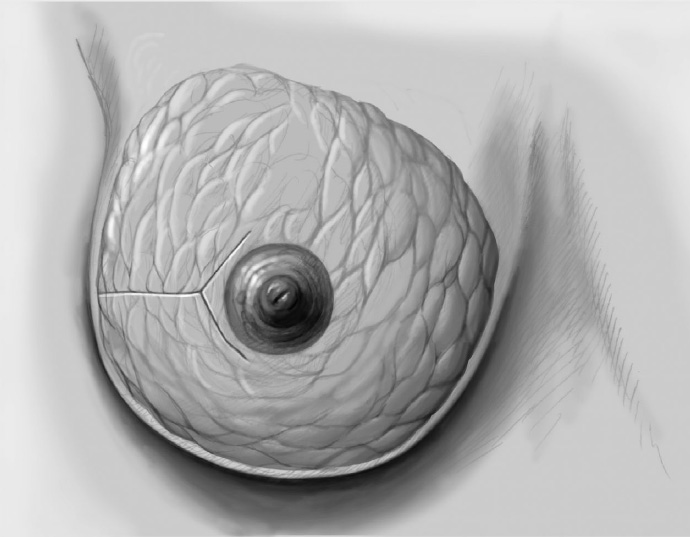

The mobilized breast lobes are rotated into the defect and approximated by interrupted sutures. Complete covering of the defect is desirable.

The skin is closed in two layers with recentering of the nipple–areola complex using interrupted sutures (Vicryl 3–0) according to the preoperative de-epithelialization pattern, which can be corrected at this time.

The skin is closed with an intracutaneous continuous monofilament suture.

The tumor is resected oncologically from the exposed breast with further resection if necessary. Circular reduction of the breast is performed in addition, ensuring that the central pedicle is not narrowed to an hourglass shape.

For internal modeling, it is advisable to reshape the reduced breast with interrupted sutures and fix it to the chest wall, especially medially, laterally, and superiorly.